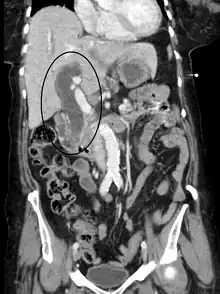

Biliary-tract dilation due to obstruction as seen on CT scan (frontal plane)

Most people presenting with jaundice have various predictable patterns of liver panel abnormalities, though significant variation does exist. The typical liver panel includes blood levels of enzymes found primarily from the liver, such as the aminotransferases (ALT, AST), and alkaline phosphatase (ALP); bilirubin (which causes the jaundice); and protein levels, specifically, total protein and albumin. Other primary lab tests for liver function include gamma glutamyl transpeptidase (GGT) and prothrombin time (PT).[37] No single test can differentiate between various classifications of jaundice. A combination of liver function tests and other physical examination findings is essential to arrive at a diagnosis.[38]

Medical imaging such as ultrasound, CT scan, and HIDA scan are useful for detecting bile-duct blockage.[41]